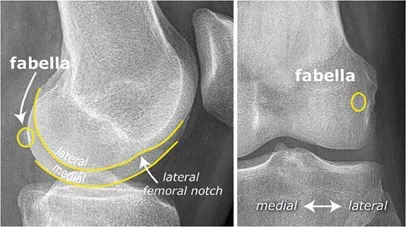

The Fabella - Normal Variant

- If there was calcification in a specific area, itâs called Fabella.